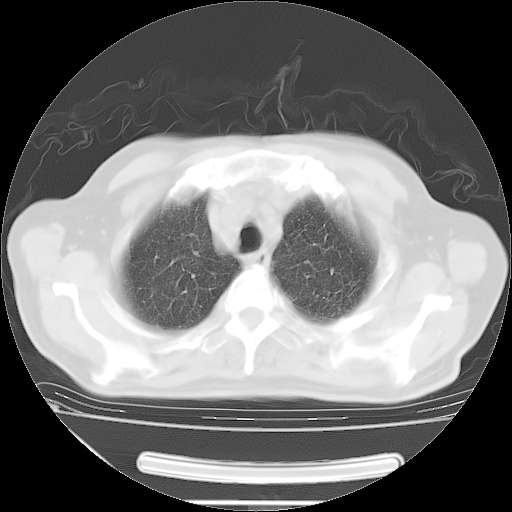

今天复查肺部CT,发现双肺广泛磨玻璃样改变。所以我把3月19日和5月9日相隔50天的肺部CT上传。请大家会诊。

5月9日肺部CT(在4月27日齐鲁医院肺部CT描述部分肺组织磨玻璃样改变,12天后肺组织广泛磨玻璃样改变)

大致读了系列胸部CT:纵隔窗无明显异常,肺窗:从4、27至今:主要是双肺中下野外带可见毛玻璃样改变,目前处于急性肺泡炎阶段,至于原因考虑1、结替组织或胶原血管性疾病所致?2、恶性疾病如恶组在肺部所致的表现或细支气管肺泡癌?3、药物或其它原因如肺蛋白沉着症所致肺泡炎目前不太可能?总之,明天就去请我院的呼吸科、感染科、血液科和临免专家会诊哈。